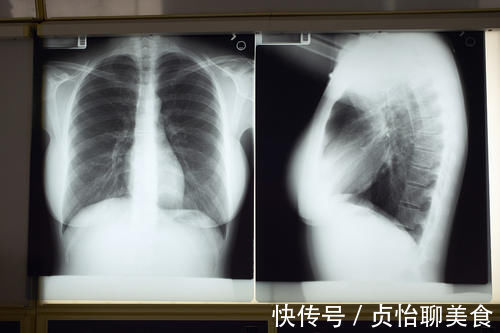

检查|胸片检查中经常出现的“肺纹理增粗”、“肺纹理增重”,严重吗?

你好,我是知心蓝医生。先说答案,拍片报告单上如果只写“肺纹理增粗”,只是一个放射影像的描述,一般不能作为诊断某一疾病的标准,更谈不上严重不严重。蓝医生在临床上也会碰到大量的这样的患者,由于要完全解释这个问题需要花一些时间,但是呢,临床上常常又比较忙,时间没那么充裕,所以往往只回答患者说“这个问题不大”,其实并没有那么简单。趁这个机会就给大家讲讲什么是肺纹理?哪些疾病会导致肺纹理增粗?拍片报告提示肺纹理增粗该怎么办?

【 检查|胸片检查中经常出现的“肺纹理增粗”、“肺纹理增重”,严重吗?】肺纹理是啥:胸部x片上提示的肺纹理其实就是气管、动脉、静脉,共同汇合在一起形成的影子。因为他们是紧密相邻,有时又有重叠,在胸片上根本就没有办法区分哪一个是气管,哪一个是动脉,哪一个是静脉,所以把他们重叠的影子统称为肺纹理。

肺纹理如何分布:可想而知,由于靠近中间的气管、动脉、静脉都相对比较粗大,所以正常情况下,胸部x片靠近中间的部分会纹理比较明显,越靠外边缘越不明显,到了外1/3,肺纹理就很细小了,因为那里只有一些毛细血管和肺泡,就像拿着一根细线来拍照,看不出什么东西来。